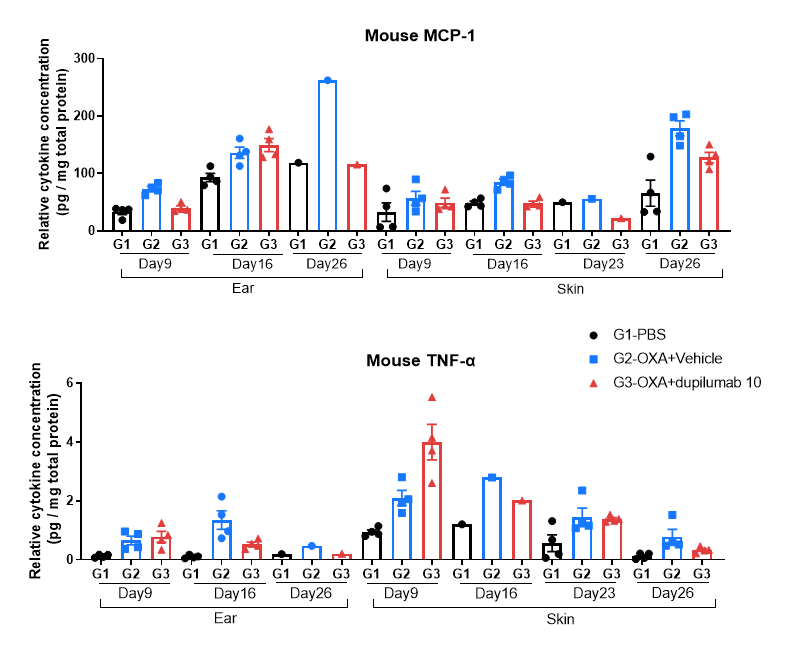

Protein expression analysis in OXA-induced AD model of B-hIL4/hIL4RA mice by Luminex.

Ear and skin samples of modeling area were collected from at day 9, 16, 26 and 26 and analyzed by Luminex. Tissue sample homogenate supernatants were loaded for detection.

Protein expression analysis in OXA-induced AD model of B-hIL4/hIL4RA mice by MSD.

Ear and skin samples of modeling area were collected from at day 9, 16, 26 and 26 and analyzed by Luminex. Tissue sample homogenate supernatants were loaded for detection.